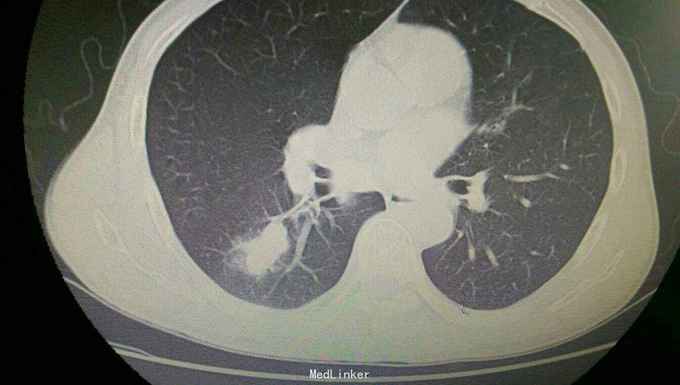

患者入院后,拟行左颌下肿块切除,在术前检查,术前准备时,常规胸片发现右侧肺部肿块,进一步行颈部及胸部ct检查,提示左颌下淋巴结肿大,转移性可能。右下肺周围性肺癌伴右肺门及纵膈多发淋巴转移考虑。决定先行左颌下肿块切除,明确诊断。术后病理示:左(左颌下腺)淋巴结转移性癌,来源首先考虑为肺。患者及家属考虑为晚期肿瘤,拒绝进一步手术治疗及化疗,下颌部切口愈合拆线后,出院。

患者出院后,门诊服中药治疗,定期复查。 讨论:患者因左颌下肿块前来就诊,术前检查发现肺部肿块,一元论考虑,应为肺部肿瘤转移所致。而且手术后病理亦证实。关键当下颌部出现肿块,应考虑肿块性质的鉴别。1.应考虑颌下肿块与颈部淋巴结的鉴别,尤其是无痛性肿块,要和淋巴结核及肿瘤等鉴别。2要和周围组织的肿瘤如甲状腺,鼻咽癌等浸润转移鉴别。3.要考虑纵膈,肺等远处转移。该患者为右下肺肿瘤已向纵膈及颈部,颌下转移,但患者临床表现仅有左颌下肿块,无胸闷气急,无咳嗽咳痰,虽ct检查发现纵膈及颈部多发淋巴结肿大,患者却无上腔静脉回流受阻,颈部浅表淋巴结未能扪及。该病例提示我们,当患者颈部出现肿块,应仔细检查,多些鉴别,以免漏诊。